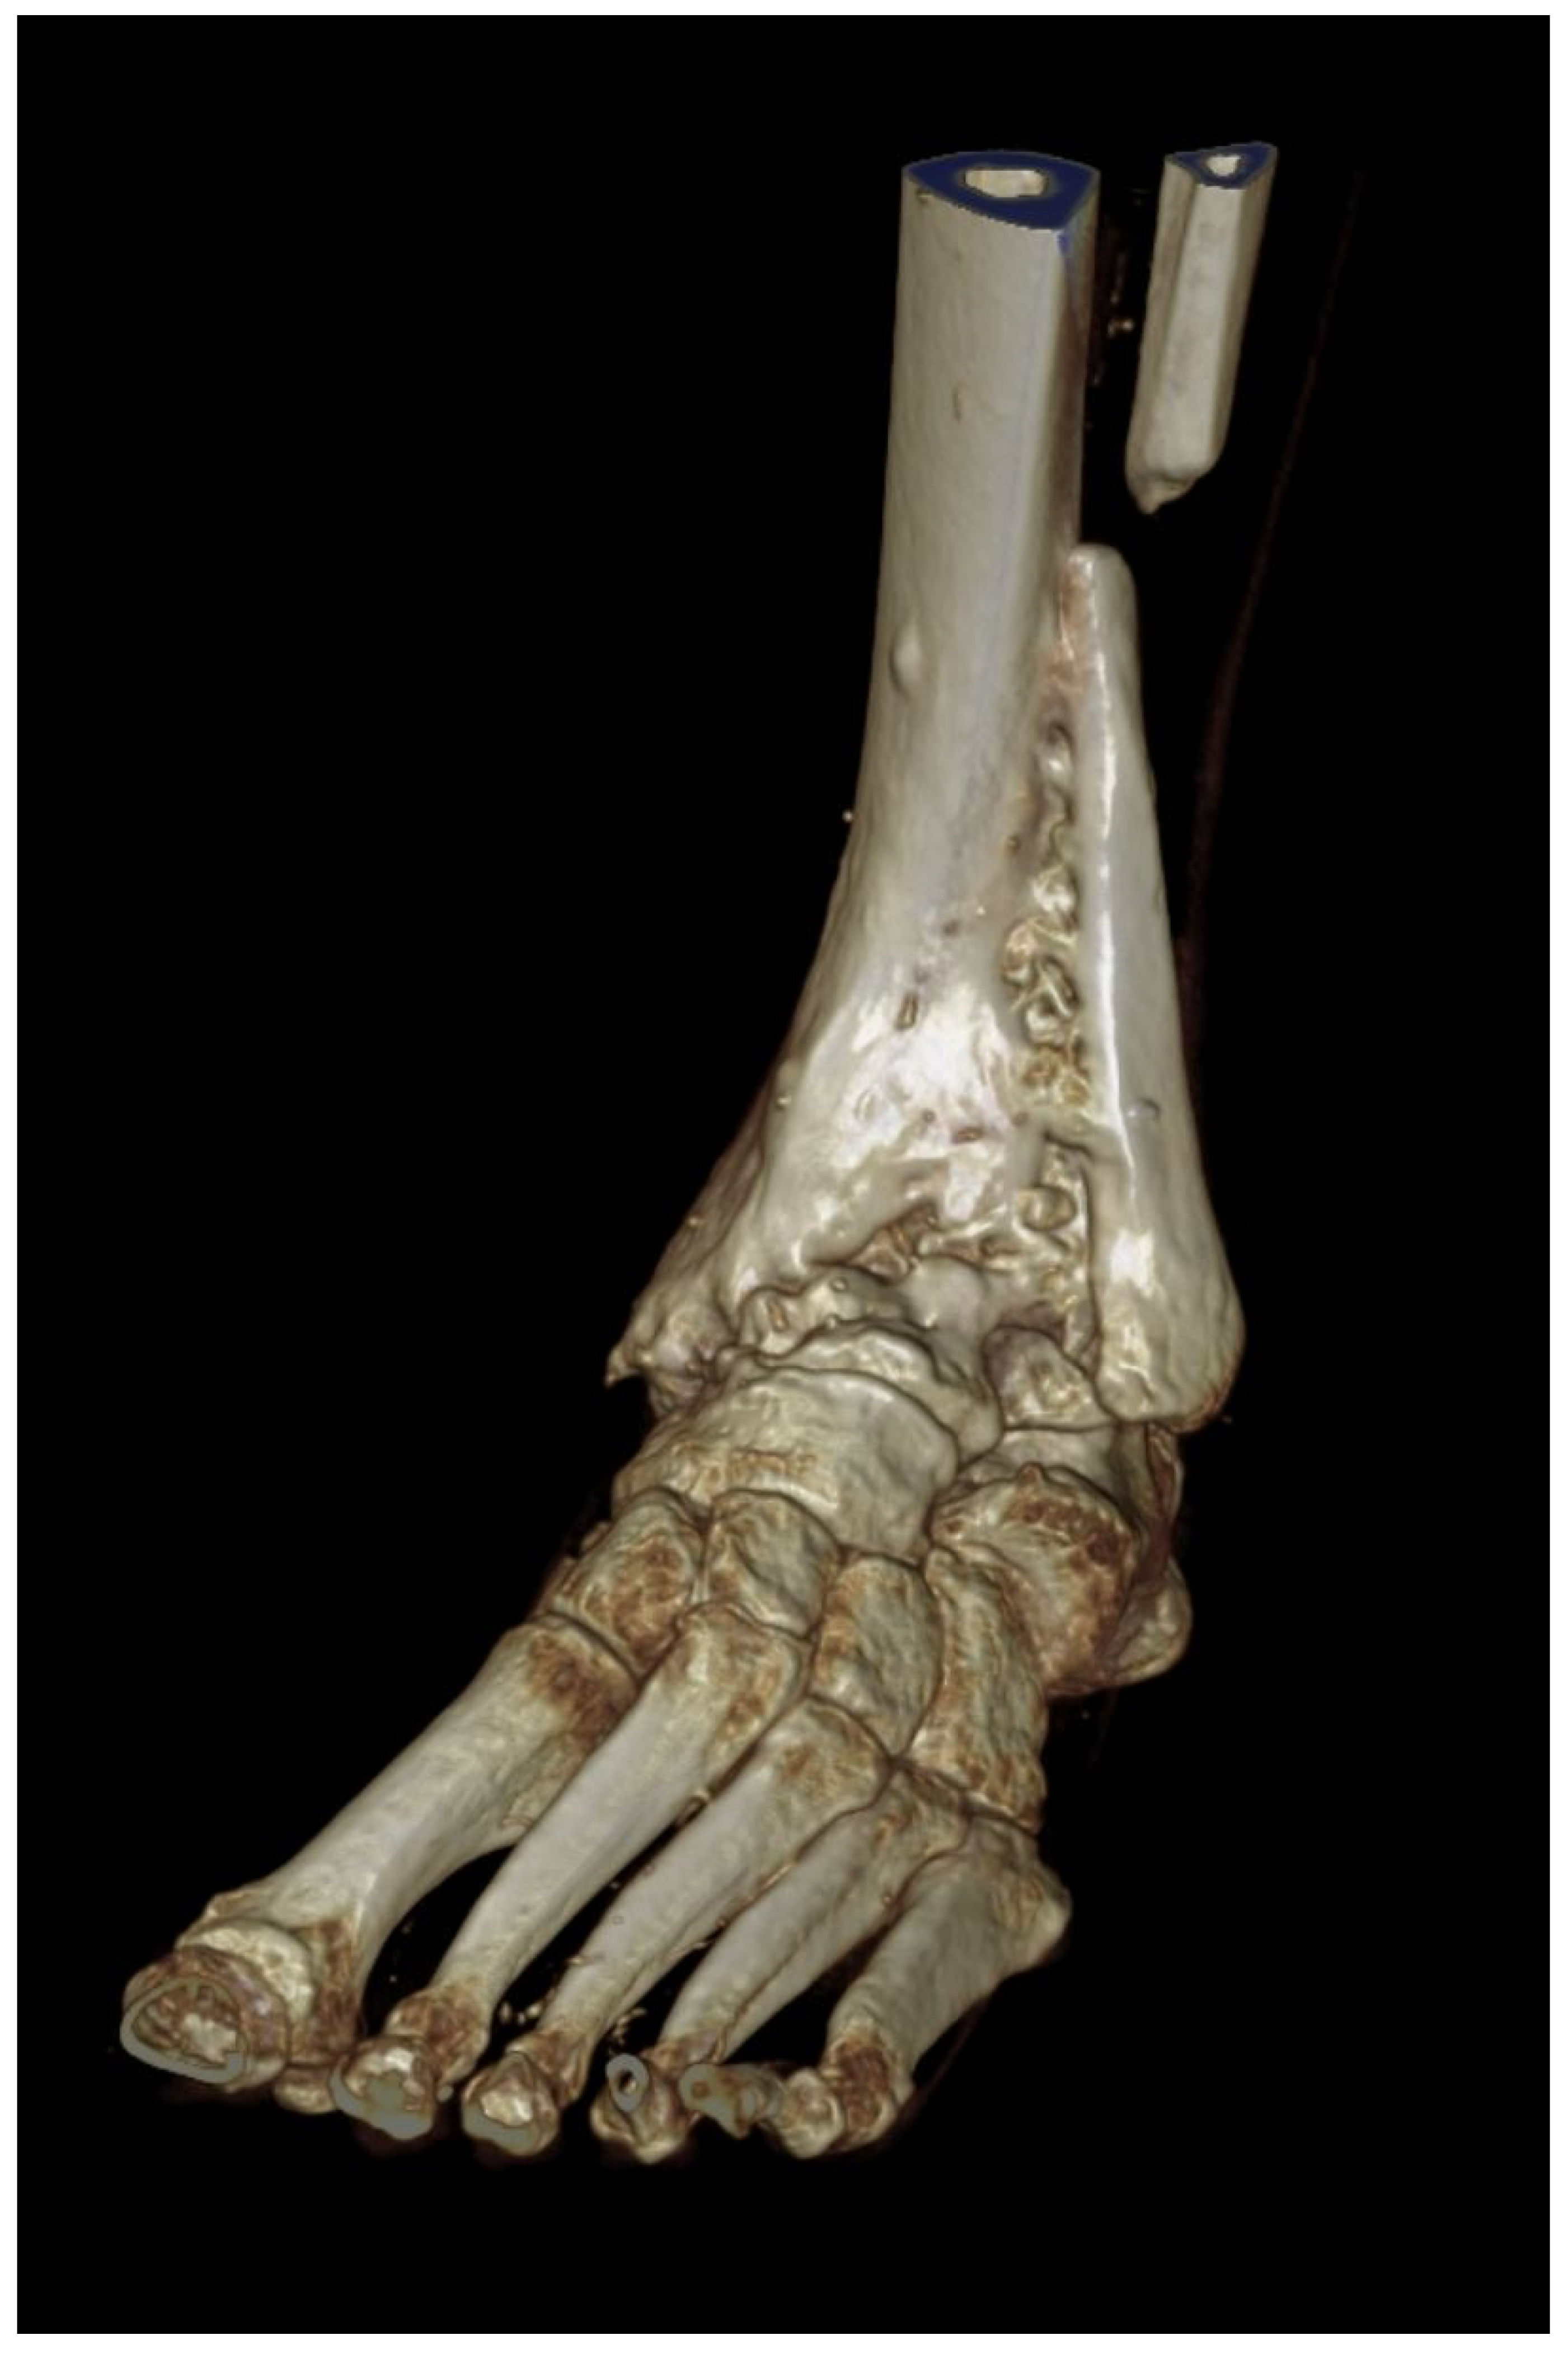

A 3D scan was performed after 1 year (Figure 11). The arthrodesis of the fibula with the tibia is visible.

Figure 11.

ROW-CT-3D-reconstruction 1 year after surgery. The arthrodesis of the fibula with the tibia is clearly visible.